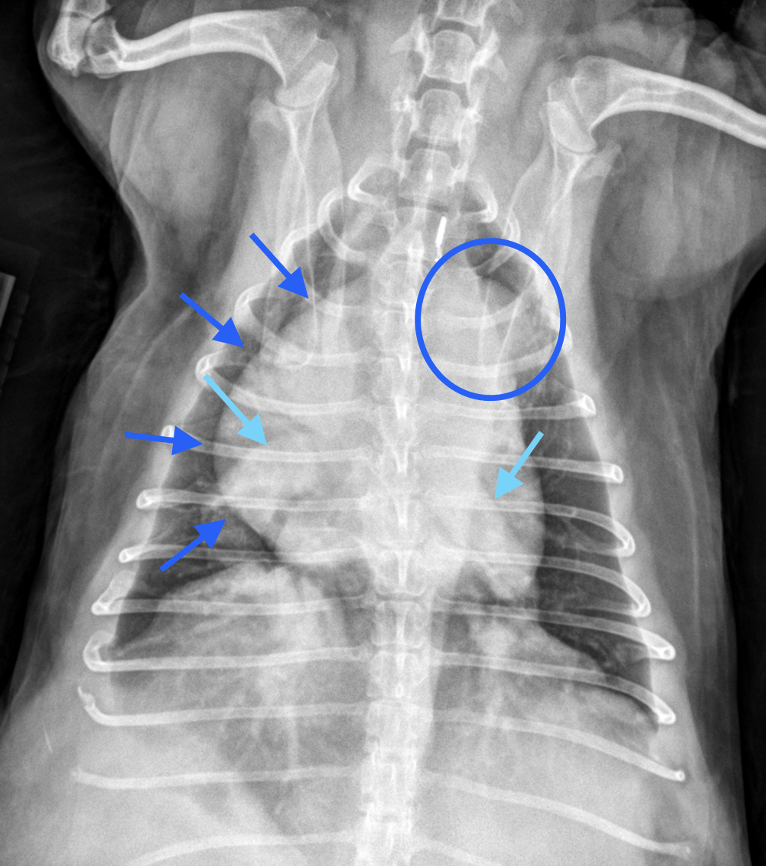

Dr. Anna Adrian, MS, DACVR, antwortet: Vielen Dank für die Zusendung dieses interessanten Falles. Es liegen eine links- und rechtslaterale sowie eine ventrodorsale Thoraxaufnahme vor. In allen drei Projektionen zeigt sich eine ausgeprägte rechtsseitige Kardiomegalie, die mit einer dorsalen Verlagerung der Trachea sowie einem vermehrten Kontakt des Herzens zum Sternum einhergeht (Bild 1, dunkelblaue Pfeilköpfe). In der ventrodorsalen Projektion imponiert die Rechtsherzvergrößerung als typische „reverse D-Form“ (Bild 2, dunkelblaue Pfeile). Zusätzlich fällt in dieser Ansicht auf Höhe der 2-Uhr-Position eine Vorwölbung auf, die einer Dilatation des Truncus pulmonalis entspricht (Bild 2, dunkelblauer Kreis).

Die kaudalen lobären Pulmonalarterien sind hochgradig erweitert, überschreiten deutlich die Breite der 9. Rippe und zeigen einen geschlängelten Verlauf (Bild 1 und 2, hellblaue Pfeile). Zur Erinnerung Venen liegen in der VD-Aufnahme zentral und in der lateralen Aufnahme ventral, wohingegen Arterien lateral und dorsal gelegen sind. Die Vena cava caudalis erscheint geringgradig dilatiert. Das Lungenparenchym weist insgesamt ein leicht- bis mittelgradig ausgeprägtes bronchointerstitielles Muster auf. Im kranialen Abdomen ist eine kraniale abdominale Organomegalie erkennbar, sowie geringgradige Heterogenität des abdominalen Fettgewebes (Bild 1, hellblau gestricheltes Rechteck). Dieser Befund ist vereinbar mit einer Splenomegalie +/- Hepatomegalie und geringgradiger Aszites. Die übrigen abdominalen Strukturen erscheinen unauffällig.